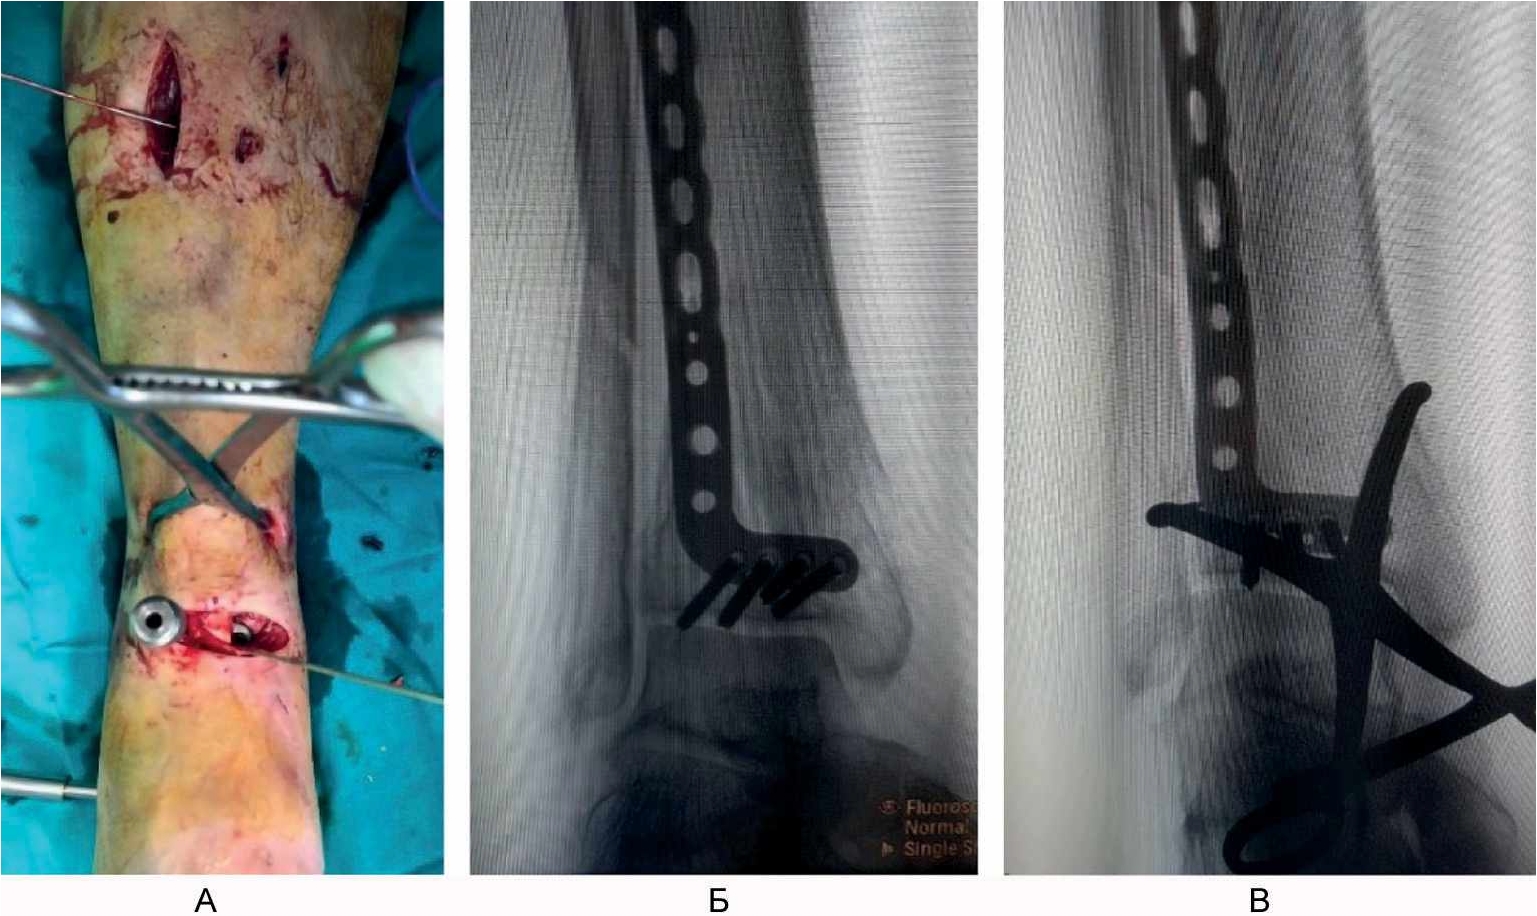

Выполнили поперечный разрез кожи и поверхностной фасции на передней поверхности голени на 1–2 см выше проекции щели голеностопного сустава. Путем продольной тупой диссекции сформировали 2 окна для доступа к большеберцовой кости между проксимальной и дистальной порциями удерживателя сухожилий разгибателей: 1-е – между длинным разгибателем I пальца стопы и длинным разгибателем пальцев стопы, 2-е – латеральнее длинного разгибателя пальцев стопы. Через сформированные окна снизу вверх эпипериостально ввели анатомически предызогнутую пластину для дистального отдела большеберцовой кости до тех пор, пока дистальный ее конец не достиг уровня субхондрального слоя большеберцовой кости. Затем пластина была предварительно фиксирована к кости спицей Киршнера. Окончательную репозицию перелома в метафизарной зоне выполнили чрескожно с использованием остроконечных репозиционных щипцов. На уровне проксимального конца пластины на переднелатеральной поверхности голени осуществили проксимальный разрез кожи и мягких тканей длиной 3 см, минимально необходимый для визуализации пластины. Пластину фиксировали к кости винтами с угловой стабильностью, введя через дистальный и проксимальный доступы ниже и выше зоны перелома, соответственно, по 4 винта. Обнажение зоны метафиза и области перелома не выполняли, что сохранило перифрактурную гематому и создало оптимальные условия для сращения перелома (рис. 4).

Рис. 4. Малоинвазивный остеосинтез минимизирует ятрогенную травму мягких тканей и нарушение кровоснабжения отломков кости. А – закрытая репозиция остроконечными репозиционными щипцами; Б, В – интраоперационные рентгенограммы при установке опорной пластины.

Затем выполнили медиальный дистальный разрез кожи и мягких тканей длиной 2 см, начиная его на 2 см проксимальнее верхушки медиальной лодыжки и продолжая его в проксимальном направлении. Далее предварительно отмоделированную по форме дистального отдела большеберцовой кости линейную пластину 1/3 трубки длиной, достаточной для перекрытия зоны перелома, провели эпипериостально снизу вверх до тех пор, пока дистальный ее конец не достиг нижнего края сделанного разреза. Затем на уровне проксимального конца введенной пластины, который хорошо пальпировался под мягкими тканями на медиальной поверхности нижней 1/3 голени, выполнили вертикальный разрез кожи длиной 2 см. Разводя кожу и подлежащие мягкие ткани, проксимальный конец введенной пластины был визуализирован в ране. Затем произвели фиксацию медиальной пластины винтами диаметром 3,5 мм, введя по 2 винта дистальнее и проксимальнее зоны перелома через медиальный дистальный и медиальный проксимальный доступы соответственно (рис. 5).

Рис. 5. Малоинвазивная имплантация металлоконструкций. А – интраоперационная рентгенограмма во время установки медиальной пластины; Б, В – интраоперационный вид конечности после установки имплантатов.